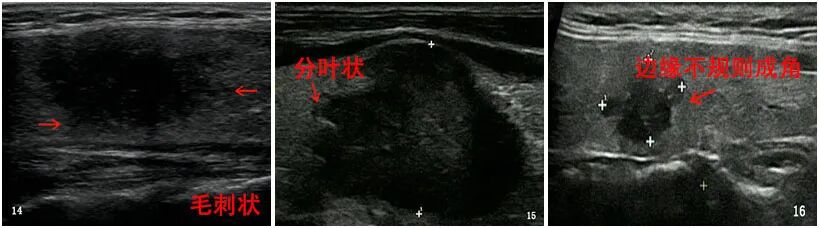

“囊性结节”完全囊性结节是无回声的,其病理结果几乎是良性结节或胶样囊肿(图1)。

有些囊性结节会被细索分成蜂窝状的多房结构,如海绵状结节(由多个微小囊性成分组成,占结节体积的50%以上)。 这些迹象强烈提示有结节。 是良性的(图2)。